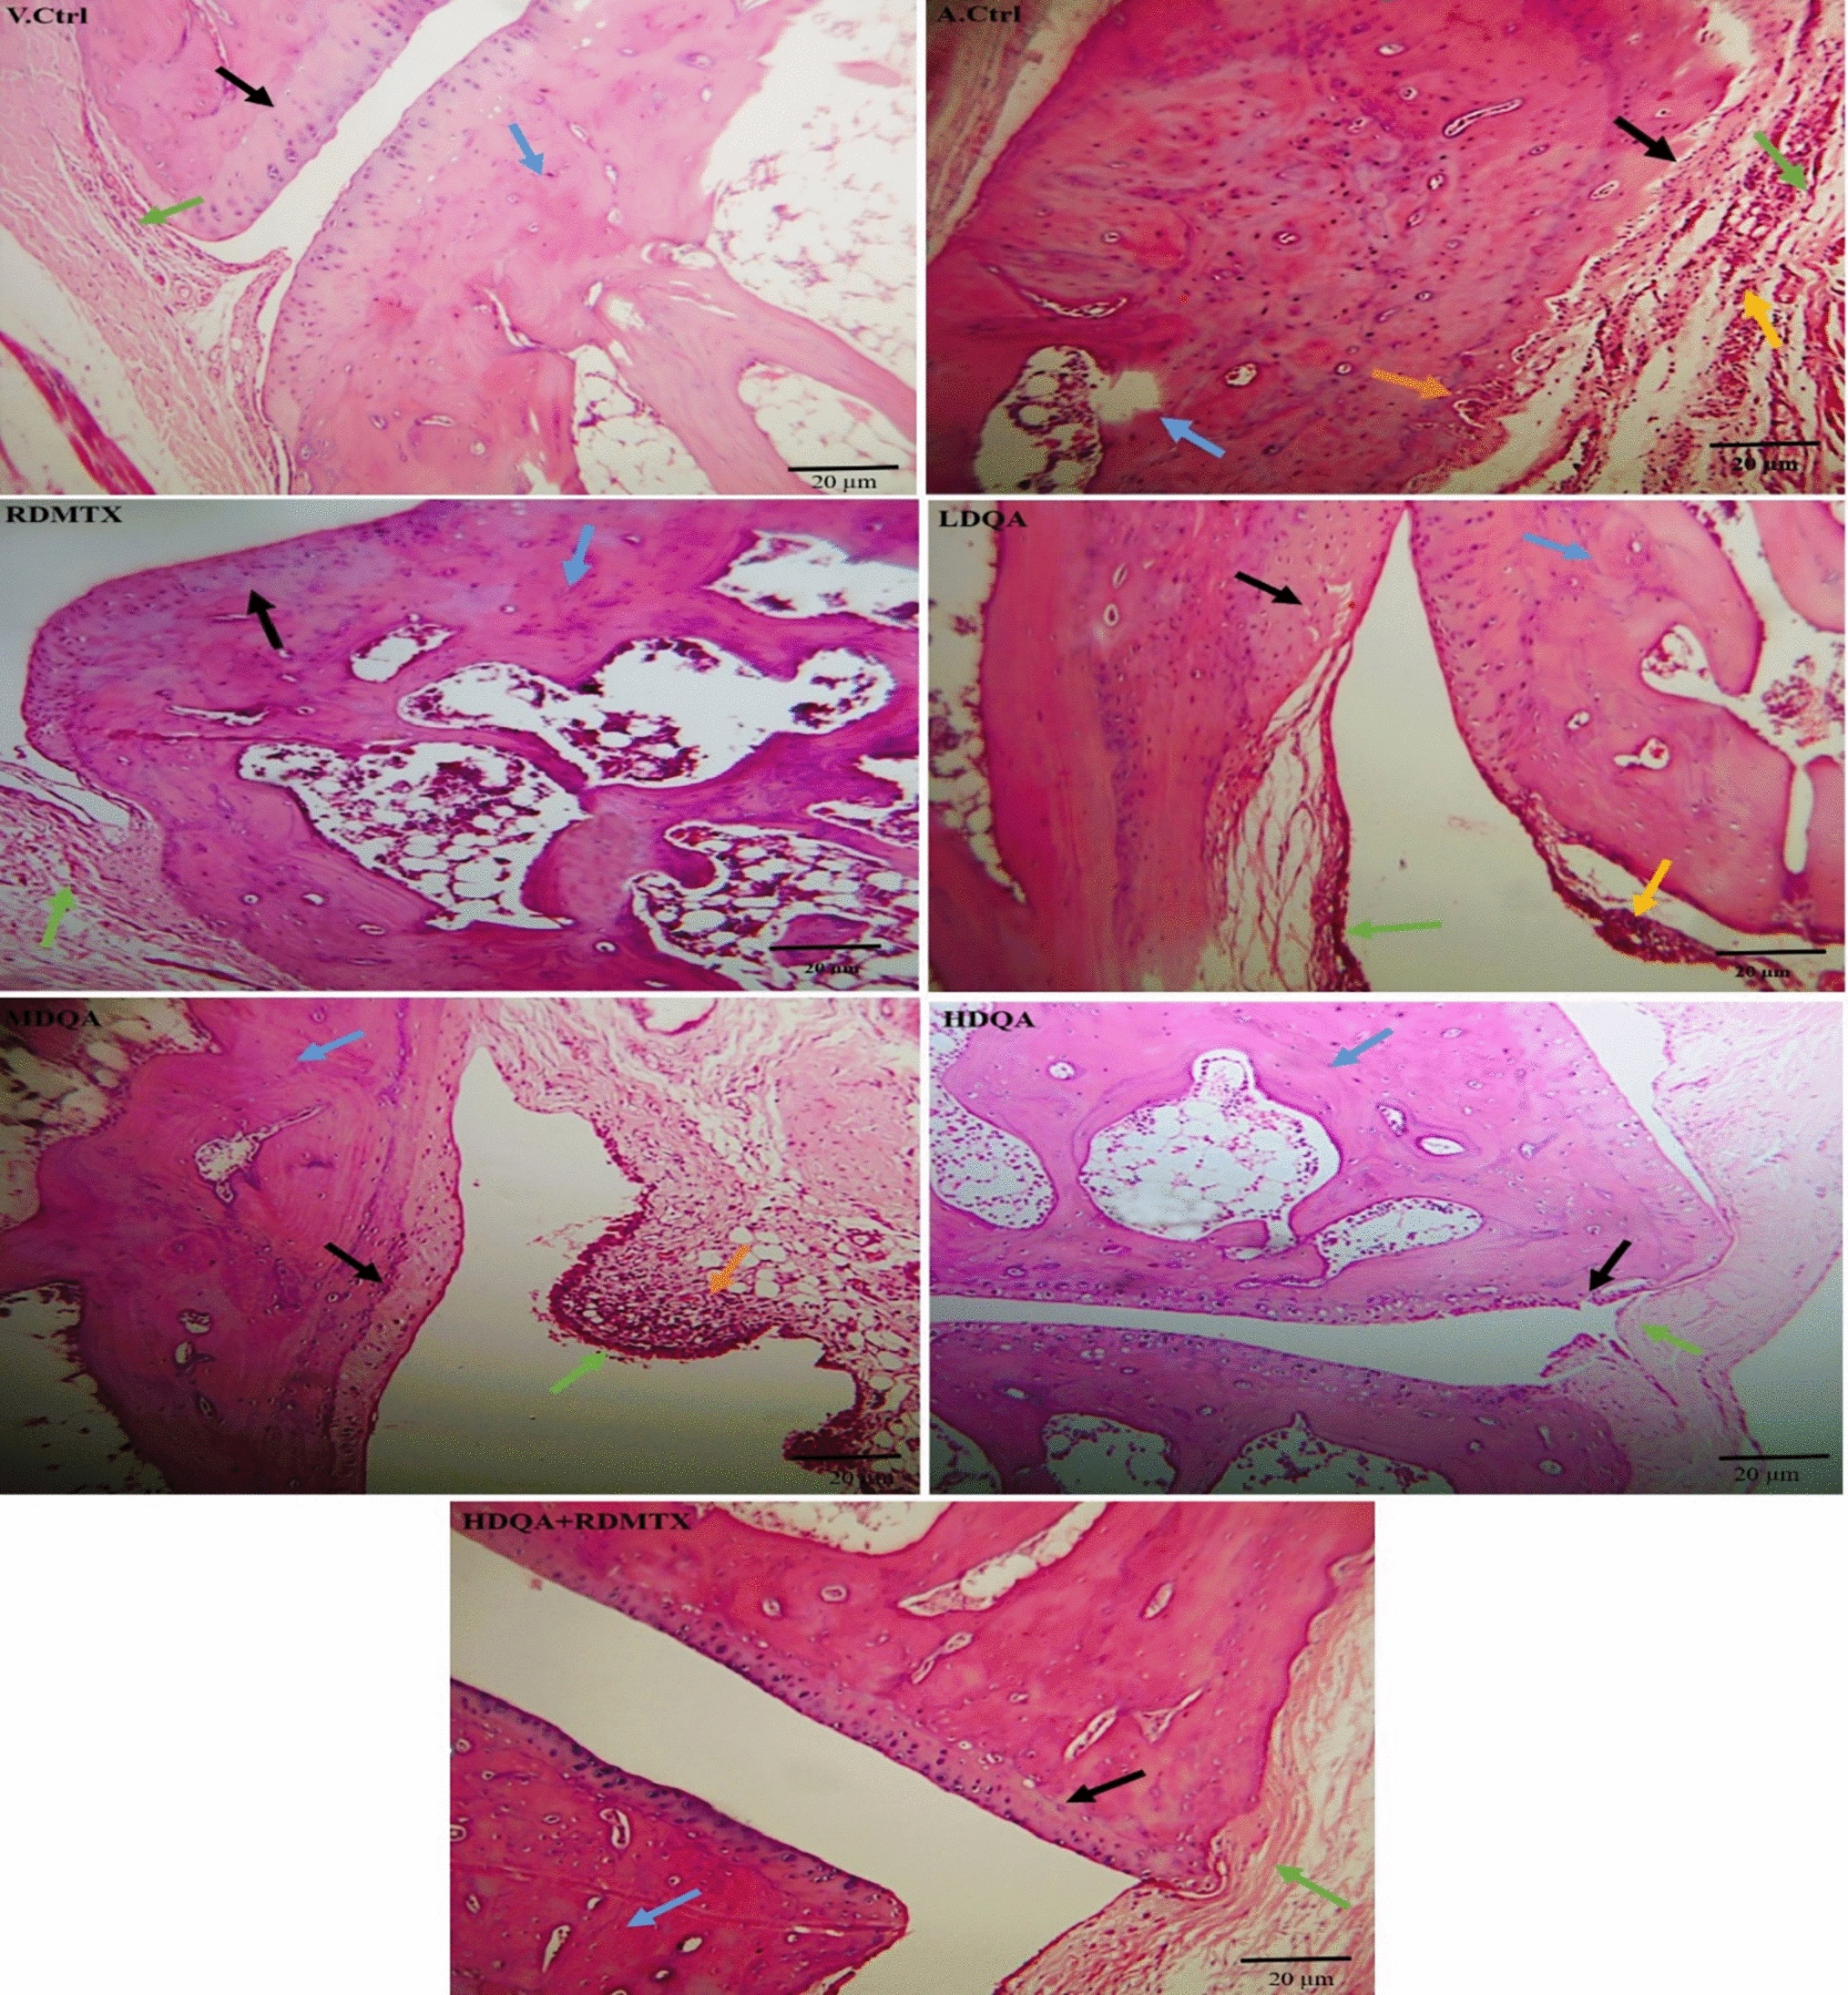

Effect of quinic acid on histopathological changes in ankle joint tissues in FCA-induced arthritic rats

Figure 6 shows that a significant (p < 0.001) increase in the severity of score of bone erosion, cartilage erosion, synovial membrane hyperplasia, infiltration of inflammatory cells, and pannus formation was observed in A. Ctrl rats as compared to V. Ctrl rats. Treatment with different doses of QA and RDMTX attenuated all the arthritic parameters, but the combination dose group (HDQA100mg/kg + RDMTX) displayed the most significant (p < 0.001) decrease in the score of bone erosion, cartilage erosion, synovial hyperplasia, infiltration of inflammatory cells, and pannus formation as compared to A. Ctrl group rats.

Fig. 6

Photomicrographs showing the histopathological section of ankle joint tissue of rats of all the experimental group (10×, H&E staining). Pannus formation (orange arrow), infiltration of inflammatory cells (yellow arrow), cartilage (black arrow), bone (blue arrow), and synovial membrane (green arrow) (color figure online)

Effect of quinic acid on histopathological changes in the arteries of ankle joint and cardiac tissues in FCA-induced arthritic rats

Figure 7 (Left aligned figures and right aligned figures) represents that A. Ctrl rats exhibited significant (p < 0.001) increase in the score of vascular congestion in arteries of the ankle joint and cardiac tissues as compared to V. Ctrl rats. Treatment with different doses of QA and RDMTX decreased the score of vascular congestion, but combination dose group (HDQA100mg/kg + RDMTX) displayed the most significant (p < 0.001) decrease in score as compared to A. Ctrl group rats.

Fig. 7

Photomicrographs showing the histopathological section of artery of rats of all the experimental group (40×, H&E staining) (left aligned figures). Photomicrograph showing the histopathological section of arteries of cardiac tissue of rats of all the experimental group (10× & 40×, H &E staining) (right aligned figures)